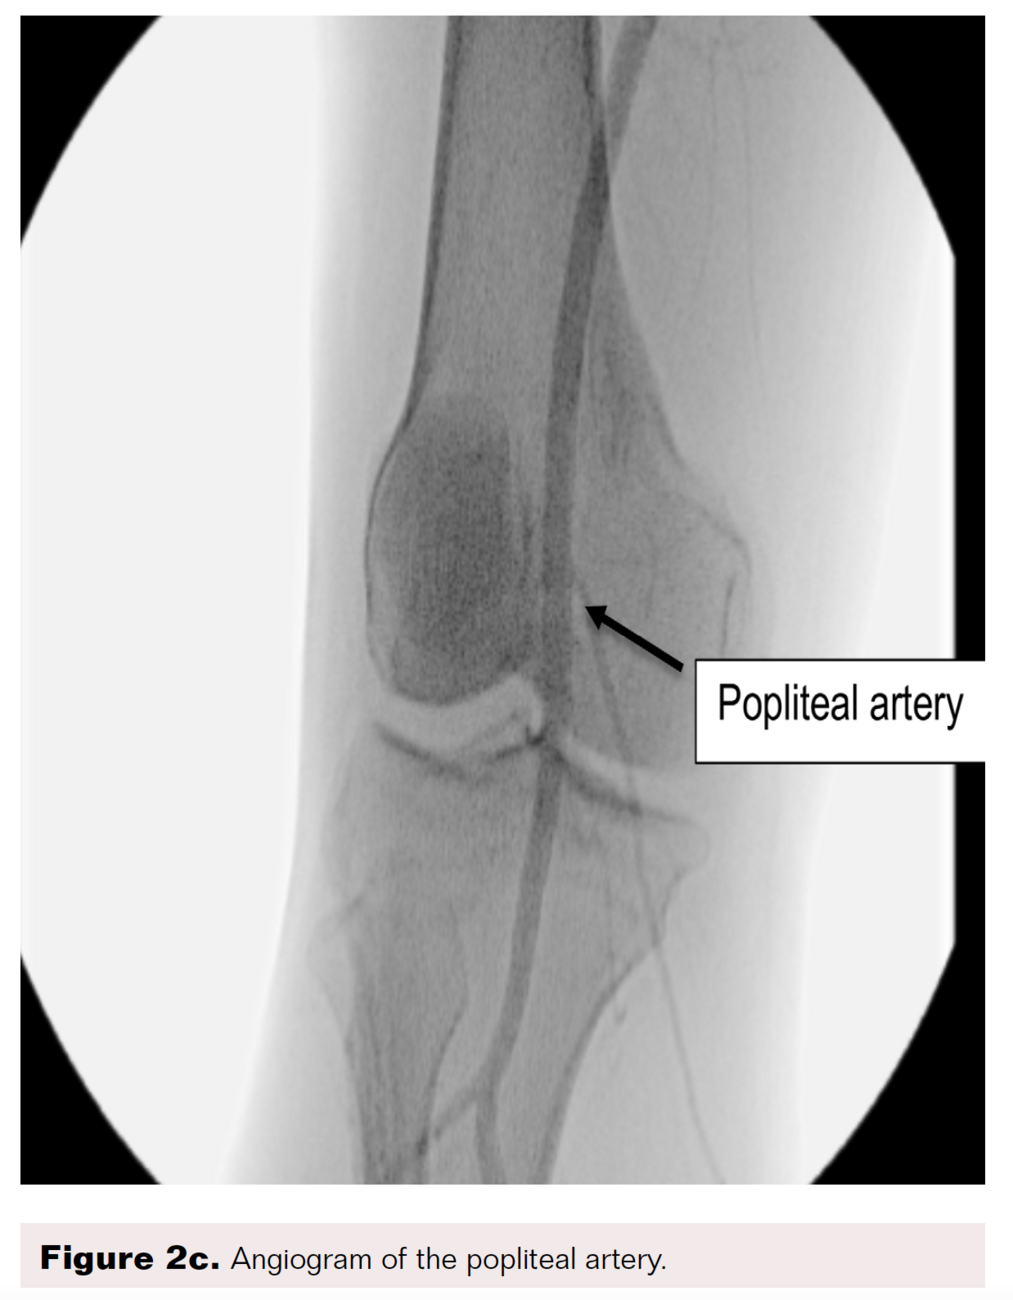

A right lower-extremity angiogram was performed using ultrasound guidance for antegrade access of the proximal superficial femoral artery (Figure 2A). Fluoroscopic acquisition demonstrated no significant disease in the superficial femoral artery (Figure 2B) and popliteal artery (Figure 2C), with no significant stenosis seen in the anterior tibial artery, PTA, and peroneal artery (Figure 2D). Pedal angiography demonstrated a complete pedal-plantar loop formed by the DPA and the lateral plantar artery (LPA) (Figure 2F).